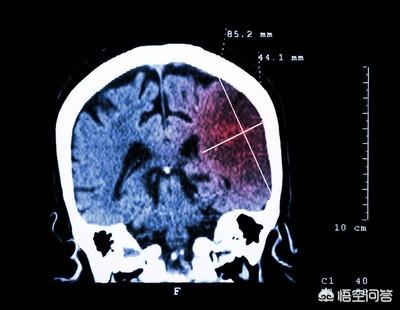

Infarctus cérébral.Il s'agit d'une maladie cérébrovasculaire courante qui survient principalement chez les personnes d'âge moyen et les personnes âgées et qui est cliniquement connue sous le nom d'"accident vasculaire cérébral ischémique".

L'infarctus cérébral est très fréquent et désigne principalement l'apparition d'une nécrose ischémique et hypoxique du tissu cérébral, entraînant un infarctus cérébral. Les causes courantes sont l'athérosclérose, l'hypertension, le diabète sucré, l'hyperlipidémie, l'embolie cardiogénique et d'autres types d'embolies dans le sang. La cause la plus fréquente est l'athérosclérose.

L'infarctus cérébral, qui est causé par une lésion nerveuse lorsqu'une artère du cerveau est bloquée et obstrue un vaisseau sanguin, apparaît souvent de manière soudaine, prenant les gens au dépourvu. En fait, de nombreuses personnes ne savent pas grand-chose sur l'infarctus cérébral, et la survenue d'un infarctus cérébral n'est pas toujours sans signes.